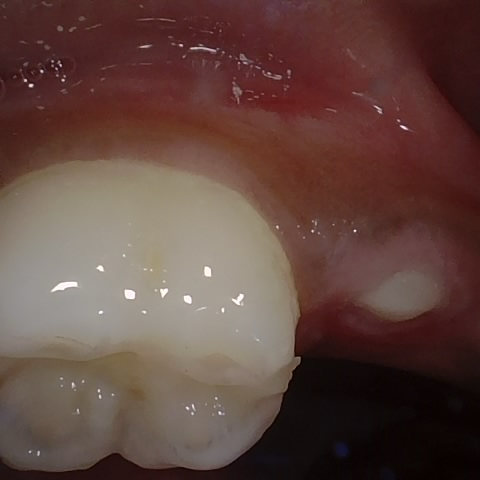

Annotated as "Good"